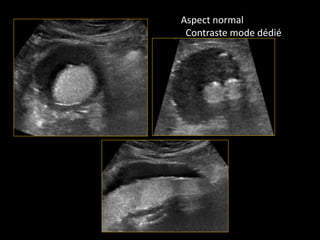

Aspect normal

Contraste mode dédié